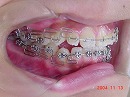

出っ歯は何がイケないの。での症例は

咬み合わせの高さが低く、下顎が後退しているところにありました。

この問題点を解決すると写真のようになります。